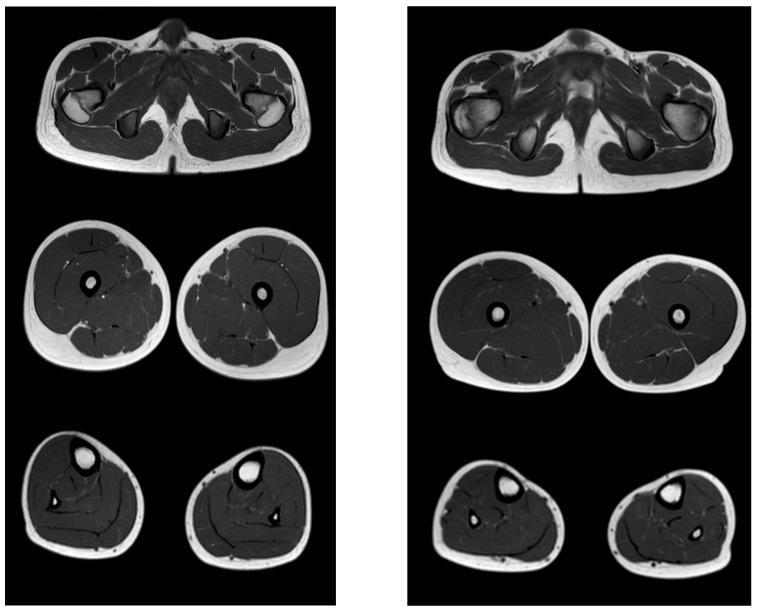

The research was aimed on the study of motor capabilities on the Motor Function Measure (MFM) scale in ambulant and non-ambulant patients with Duchenne muscular dystrophy, and to conduct a correlation analysis between the results of the MFM scale and Magnetic Resonance Imaging (MRI) data. A total of 46 boys who had genetically confirmed Duchenne muscular dystrophy (age from 2.1 to 16.7 years) and were in clinical rehabilitation were investigated. An assessment was performed according to the Motor Function Measure scale (subsections D1, D2, D3, and the total score), an MRI obtaining T1-VI of the muscles of the pelvic girdle was conducted, and the thighs and lower legs were further assessed in terms of the severity of fibrous-fat degeneration according to the Mercuri scale. In ambulant patients, the ability to stand up and move (D1) was 74.4%, axial and proximal motor functions (D2)—97.6%, distal motor functions (D3)—96.2%, and total score was 87.9%. In non-ambulant patients, the ability to stand up and move (D1) was 1.7%, axial and proximal motor functions (D2)—47%, distal motor functions (D3)—67.5%, and the total score—33.1%. A high inverse correlation (r = −0.7, p < 0.05) of the MRI data of the pelvic girdle and thighs with tasks D1, as well as a noticeable inverse correlation with tasks D2 (r = −0.6, p < 0.05) of the scale MFM, were revealed in the ambulant group of patients. In the non-ambulant group of patients, the MRI data of the lower legs muscles were characterized by a high inverse correlation (r = −0.7, p < 0.05) with tasks D3 and a noticeable inverse correlation (r = −0.6, p < 0.05) with tasks D1 of the MFM scale. Conclusion: The Motor Function Measure scale allows effective assessment of the motor capabilities of patients with Duchenne muscular dystrophy at different stages of the disease, which is confirmed by visualization of fibro-fatty muscle replacement.

本研究旨在研究肌营养不良症(Duchenne muscular dystrophy,DMD)患者的运动功能,使用运动功能测量(Motor Function Measure,MFM)量表评估其在活动和非活动患者中的表现,并对 MFM 量表的结果与磁共振成像(Magnetic Resonance Imaging,MRI)数据进行相关性分析。本研究共纳入了 46 名经基因确诊的 DMD 男孩(年龄为 2.1-16.7 岁),他们均处于临床康复阶段。研究人员对这些患者进行了 MFM 量表(D1、D2、D3 亚组和总分)评估,并进行了骨盆带肌肉的 T1-VI MRI 检查,根据 Mercuri 量表对大腿和小腿的纤维脂肪变性严重程度进行了进一步评估。在活动患者中,站立和移动能力(D1)为 74.4%,轴向和近端运动功能(D2)为 97.6%,远端运动功能(D3)为 96.2%,总分为 87.9%。在非活动患者中,站立和移动能力(D1)为 1.7%,轴向和近端运动功能(D2)为 47%,远端运动功能(D3)为 67.5%,总分为 33.1%。在活动患者中,骨盆带和大腿 MRI 数据与任务 D1 之间存在高度负相关(r = -0.7,p < 0.05),与 MFM 量表的任务 D2 之间也存在显著的负相关(r = -0.6,p < 0.05)。在非活动患者中,小腿肌肉的 MRI 数据与任务 D3 之间存在高度负相关(r = -0.7,p < 0.05),与 MFM 量表的任务 D1 之间也存在显著的负相关(r = -0.6,p < 0.05)。结论:MFM 量表能够有效评估不同疾病阶段的 DMD 患者的运动能力,这一结论通过纤维脂肪肌肉替代的可视化得到了证实。